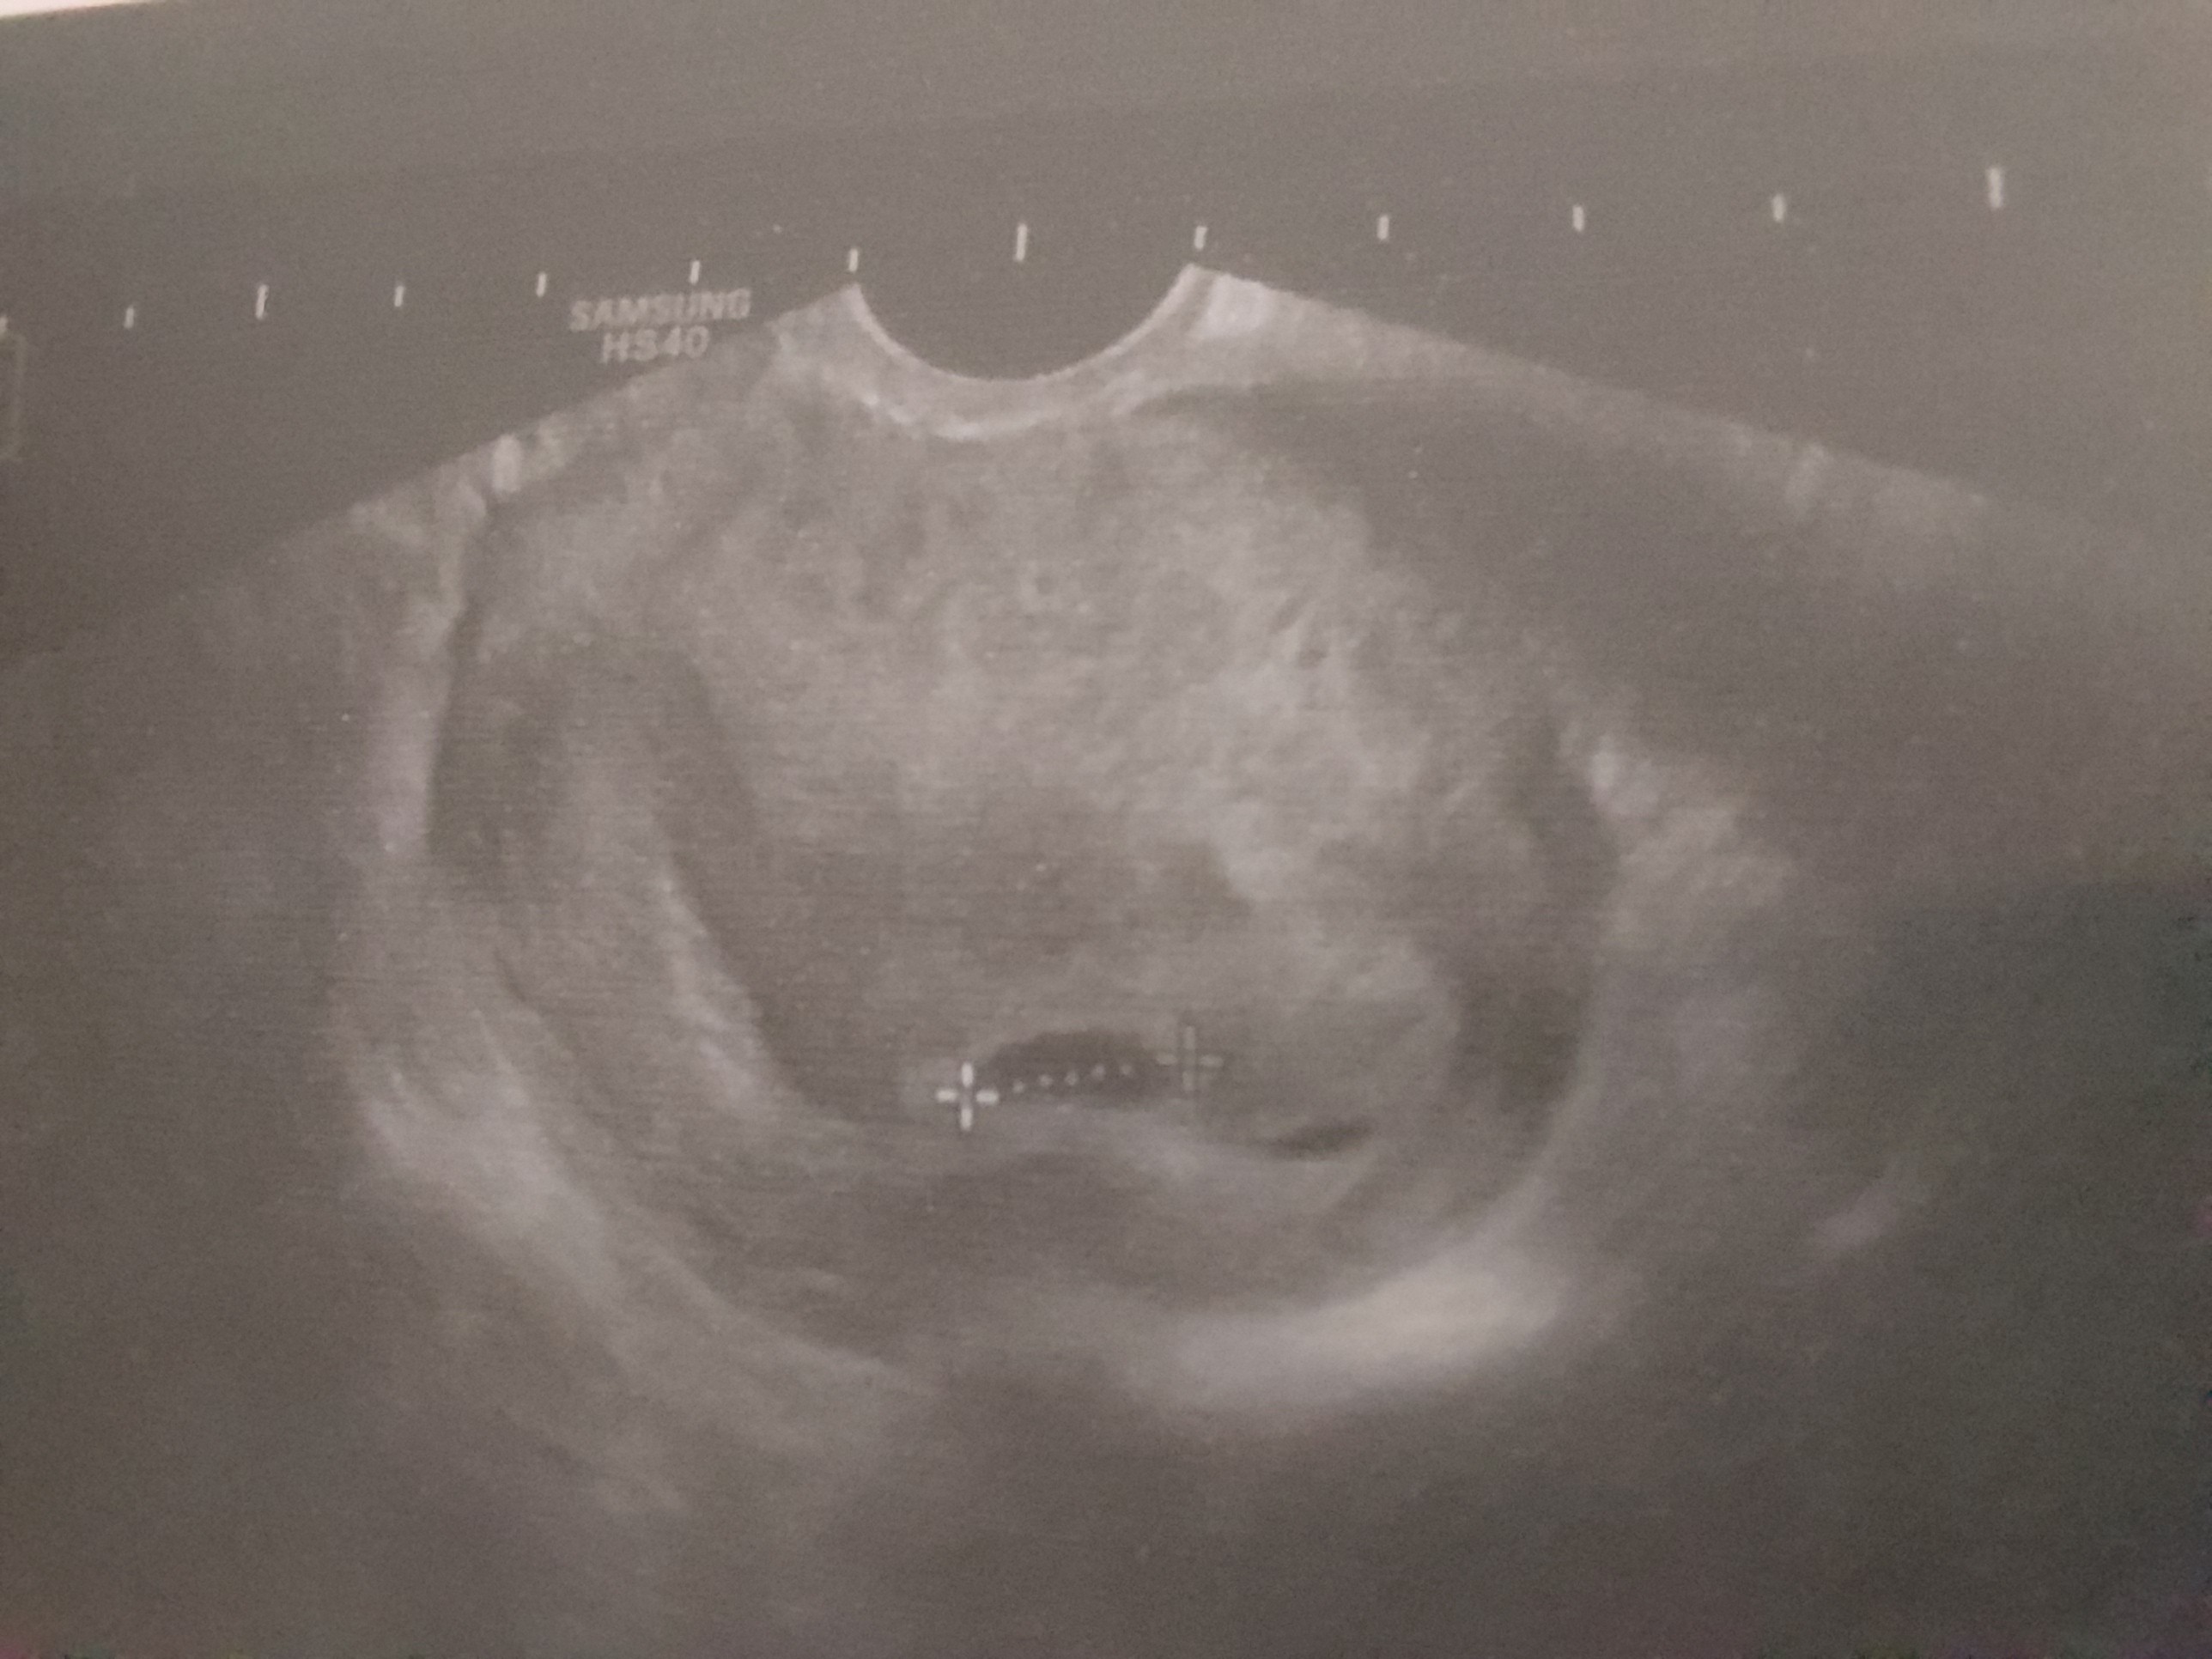

Cześć dziewczyny, ja po wizycie i w sumie tak jak myslalam, za wcześnie poszlam. A mowilam, że w przyjdę w piątek lub poniedziałek, to kazala mi jechać w środę. W drugiej ciazy byl zarodek 9 dni po 2mm pecherzyku, teraz minelo 6 dni. Jest pęcherzyk 12 mm, ale jeszcze w srodku nic nie widać. Za to pojawił się krwiaczek (widać go na zdjęciu po prawej od pecherzyka), dostalam dupka 3x dziennie i magne b6 3x2 tabletki, powinien się wchlonac. Znow wyslala mnie na znienawidzona betę. 🙈 Bo krwiaczek może zakrwawic, i żeby było wiadomo, że ciaza się rozwija prawidłowo, a krwawienie to z krwiaka, to dziś i w piątek mam zrobic, czekam już na pierwszy wynik.